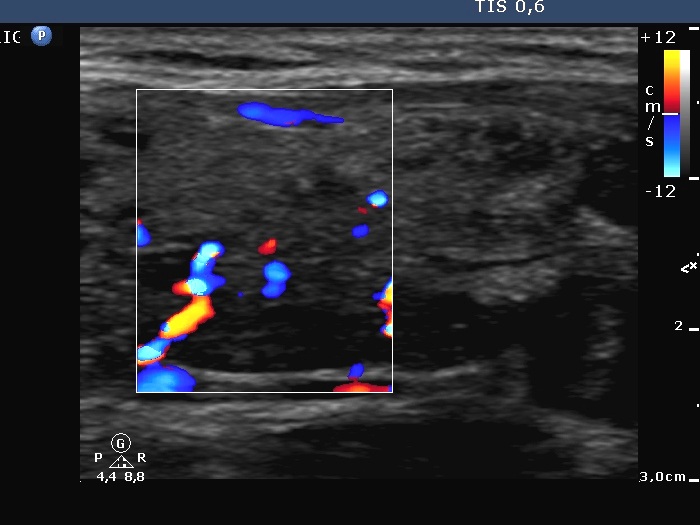

100 consecutive cases of papillary cancer - case 011

Follow-up investigation 17 months after the first visit (ultrasonographic picture 6)

Left lobe, longitudinal scan, color Doppler mode. The vascularization is average or slightly increased.